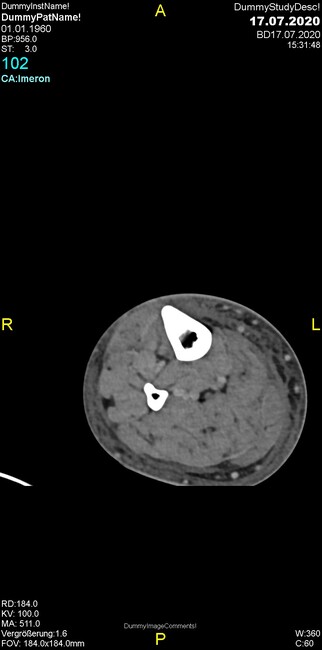

Um welche Modalitäten handelt es sich?

- Röntgen p.a. und lateral, CT coronar Knochenfenster, CT axial Weichgewebsfenster

- Röntgen p.a. und oblique, CT coronar Knochenfenster, CT axial Weichgewebsfenster

- Röntgen p.a. und lateral, CT sagittal Weichgewebsfenster, CT coronar Knochenfenster

- Röntgen p.a. und oblique, CT sagittal Knochenfenster, CT coronar Weichgewebsfenster

- Röntgen p.a. und lateral, CT coronar Weichgewebsfenster, MR axial

Was fällt in der CT im Knochenfenster auf?

- Mediale Gelenkspaltverschmälerung

- Dezente Erosion der fibulären Kortikalis

- Frakturspalt der lateralen Tibiametaphyse

- Weichgewebskalzifikationen lateral angrenzend an den Gelenkspalt

- Osteolyse der Tibiametaphyse unter Beteiligung der Kortikalis